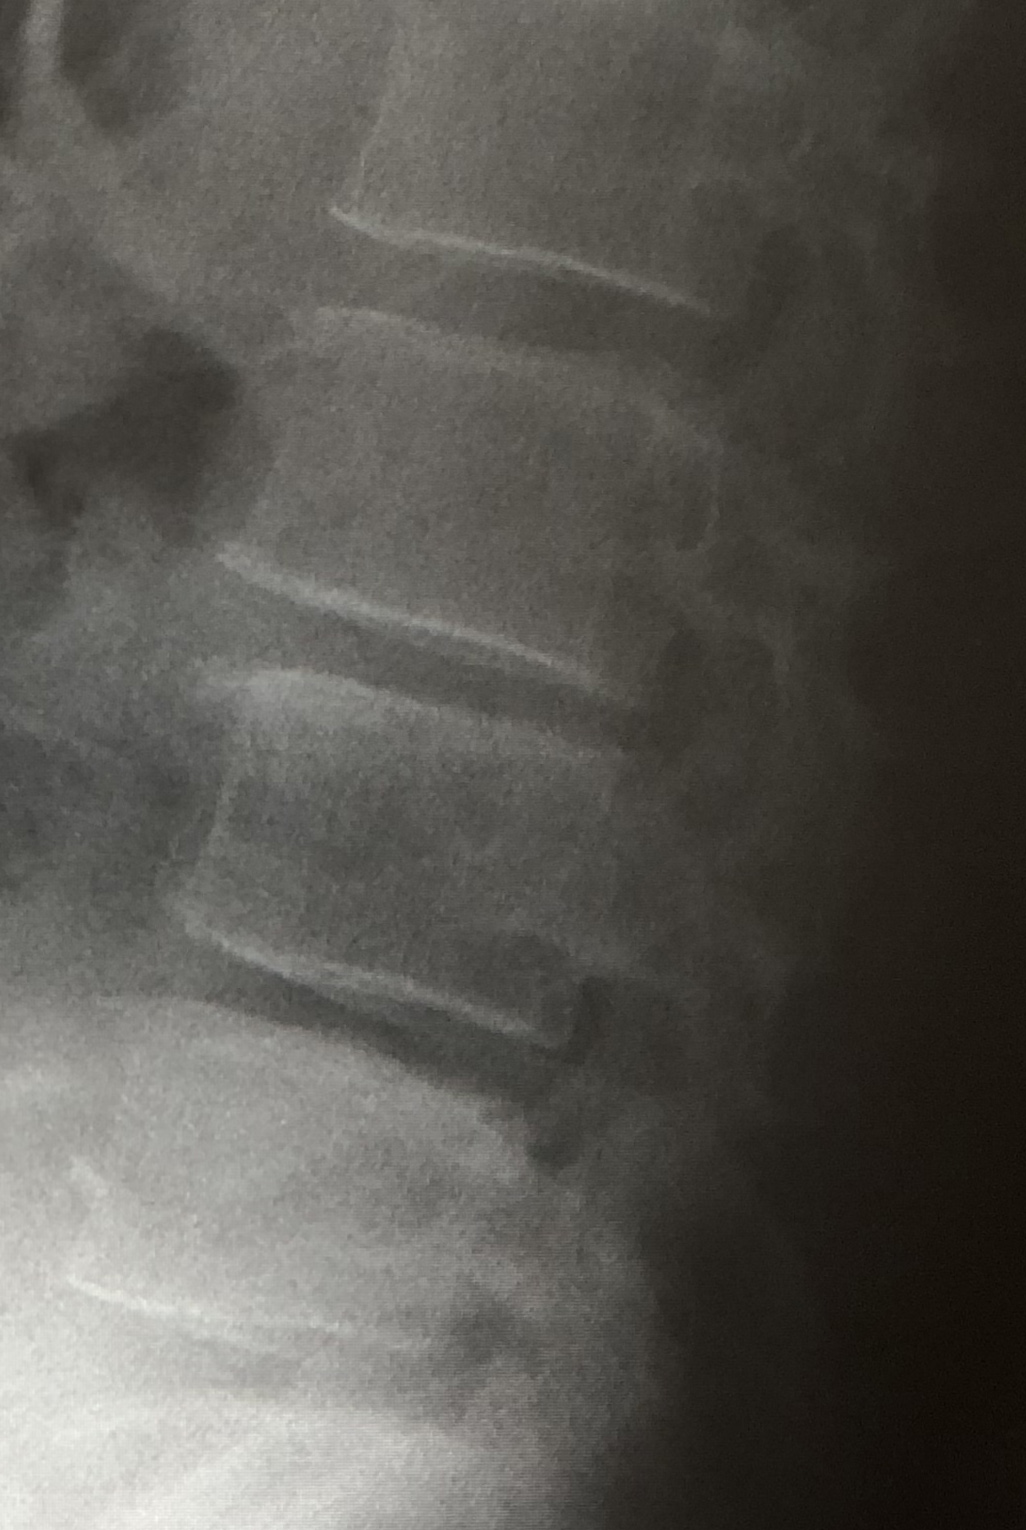

| 術前 | 術後 | |

|---|---|---|

| X線 |

|